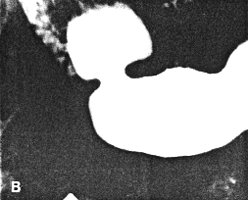

Case 37.1. D.R., 40 year old male had a long history of ethanol abuse and insulin- dependent diabetes mellitus which had been treated inadequately. For several weeks there had been dyspepsia, loss of appetite and nausea. Radiologically primary and secondary oesophageal peristaltic waves were normal. After an overnight fast the stomach contained food residues; the pyloric aperture was patent, measuring 9.0. mm in diameter (Fig. 37.1A). Gastric peristaltic waves were decreased both in frequency (i.e. less than 3 per minute) and intensity (i.e. failing to "bi-sect" the organ). The pyloric sphincteric cylinder was in a state of partial contraction most of the time (Fig. 37.1B). Cyclical contraction and relaxation of the cylinder, normally occurring at a frequency of 3 per minute (Chaps. 13, 15), was lacking. No obstructing lesion was seen at the pylorus and the duodenum appeared normal. Sonographically the gall bladder, liver, spleen and kidneys were normal; there was no ascites. The patient refused endoscopic examination.

| Fig. 37.1. A,B. Case D.R. A Food residues in stomach. Pyloric aperture patent. Gastric peristaltic activity diminished. B Pyloric sphincteric cylinder (arrows) contracted most of the time. |

Six months later, after proper diabetic control, he had improved clinically. On this occasion the stomach contained less residual food. Shallow gastric peristaltic waves were present, while the pyloric sphincteric cylinder remained partially contracted throughout the examination (Fig. 37.1C). Although this was less marked than on the previous occasion, normal cyclical activity remained absent and no maximal or complete contractions were seen. Peristaltic activity in the duodenum appeared to be decreased. Active peristaltic contractions with a fast passage of barium was noted in the jejunum. The films also showed scattered areas of calcification in the pancreas and the case was diagnosed as diabetic gastroparesis and chronic alcoholic pancreatitis. Case 37.2. T.M., 64 year old female with longstanding insulin-dependent diabetes mellitus and psychotic symptoms, was admitted with epigastric pain and episodes of vomiting. Radiological examination showed a decrease in frequency and intensity of gastric peristaltic waves; there was a lack of cyclical contraction and relaxation of the pyloric sphincteric cylinder, which remained in a state of partial contraction throughout the examination; this was associated with a patulous pyloric orifice measuring 1.2 cm in diameter. Sonographically the gall bladder, liver, spleen, kidneys and aorta were normal. The pancreas could not be visualized owing to obesity.